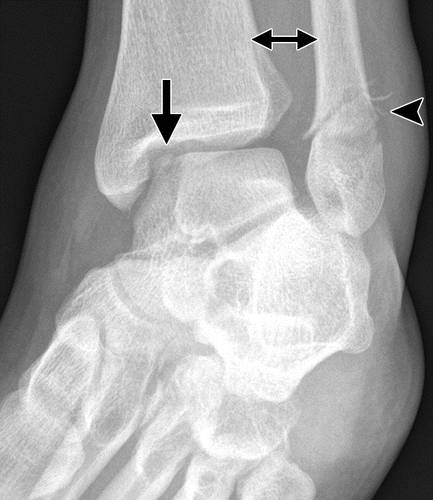

图12a内侧踝关节骨软骨骨折。 AP(a)和斜位(b)踝骨的X线照片显示椎间融合器的移位骨软骨骨折(黑色箭头)。 还注意到倾斜的骨干腓骨骨折(箭头),syndesmotic加宽(双头箭头)和内侧清晰空间加宽(白色箭头b),符合syndesmotic和三角肌韧带复杂损伤的存在。

后突骨折通常比内侧结节(Cedell骨折)(30)涉及外侧结节(Shepherd骨折)。 后部过程骨折由于跖骨屈曲引起,导致胫骨和跟骨之间的后部过程的压缩。 这也可能发生在对后踝的直接创伤。

这种损伤必须与三角骨 - 一个附件后骨小梁区分开来。 在放射照相术中,后过程的断裂显示不规则的边缘(图13),而三角骨是圆形或椭圆形,具有光滑的皮质边缘(图14)。 双侧X线照片的价值有限,因为据报道三分之二的病例是双侧的(32)。 如果射线照片不确定,应进行CT。

图13b后突骨折。 (a)右足的外侧X光片显示在距骨后方的小骨质碎片(箭头)。 (b)右脚的轴向CT图像显示后路过程骨折(箭头)以及粉碎的程度和程度。